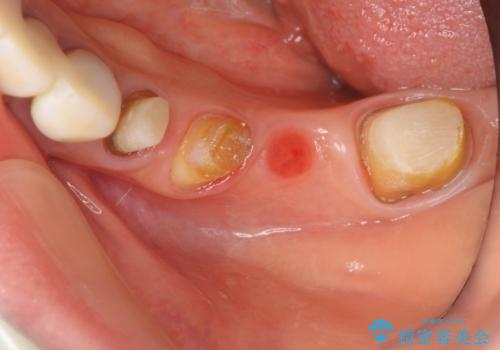

精度の高いジルコニアブリッジの製作に加え歯茎にぴったりとそわせたオベイトポンティック形態とすることで清掃性・審美性に優れたブリッジを製作します。

歯ぐきの形態にそわせ、凸型でくぼみのないオベイト型のポンティックはプラークの溜まりにくく審美性も達成できるポンティック形態です。